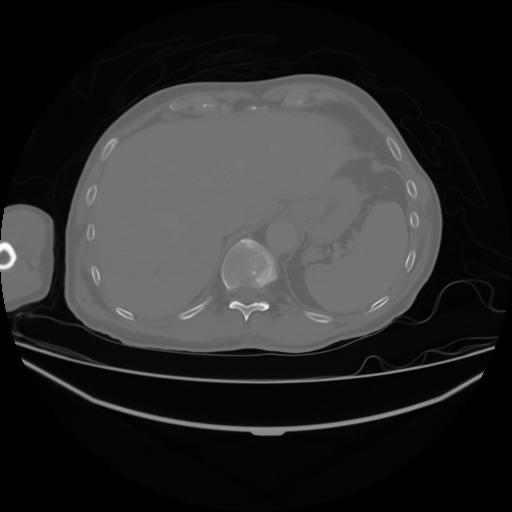

4 CUERPO,CE,Axial,3.0,CUERPO,,